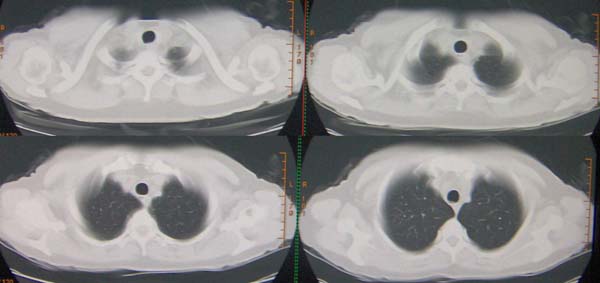

标题: CT9509:女,50岁,咳嗽,发热,38度, [打印本页]

标题: CT9509:女,50岁,咳嗽,发热,38度,

与x2653同一病人:http://www.radida.com/bbs/forum.php?mod=viewthread&tid=28727